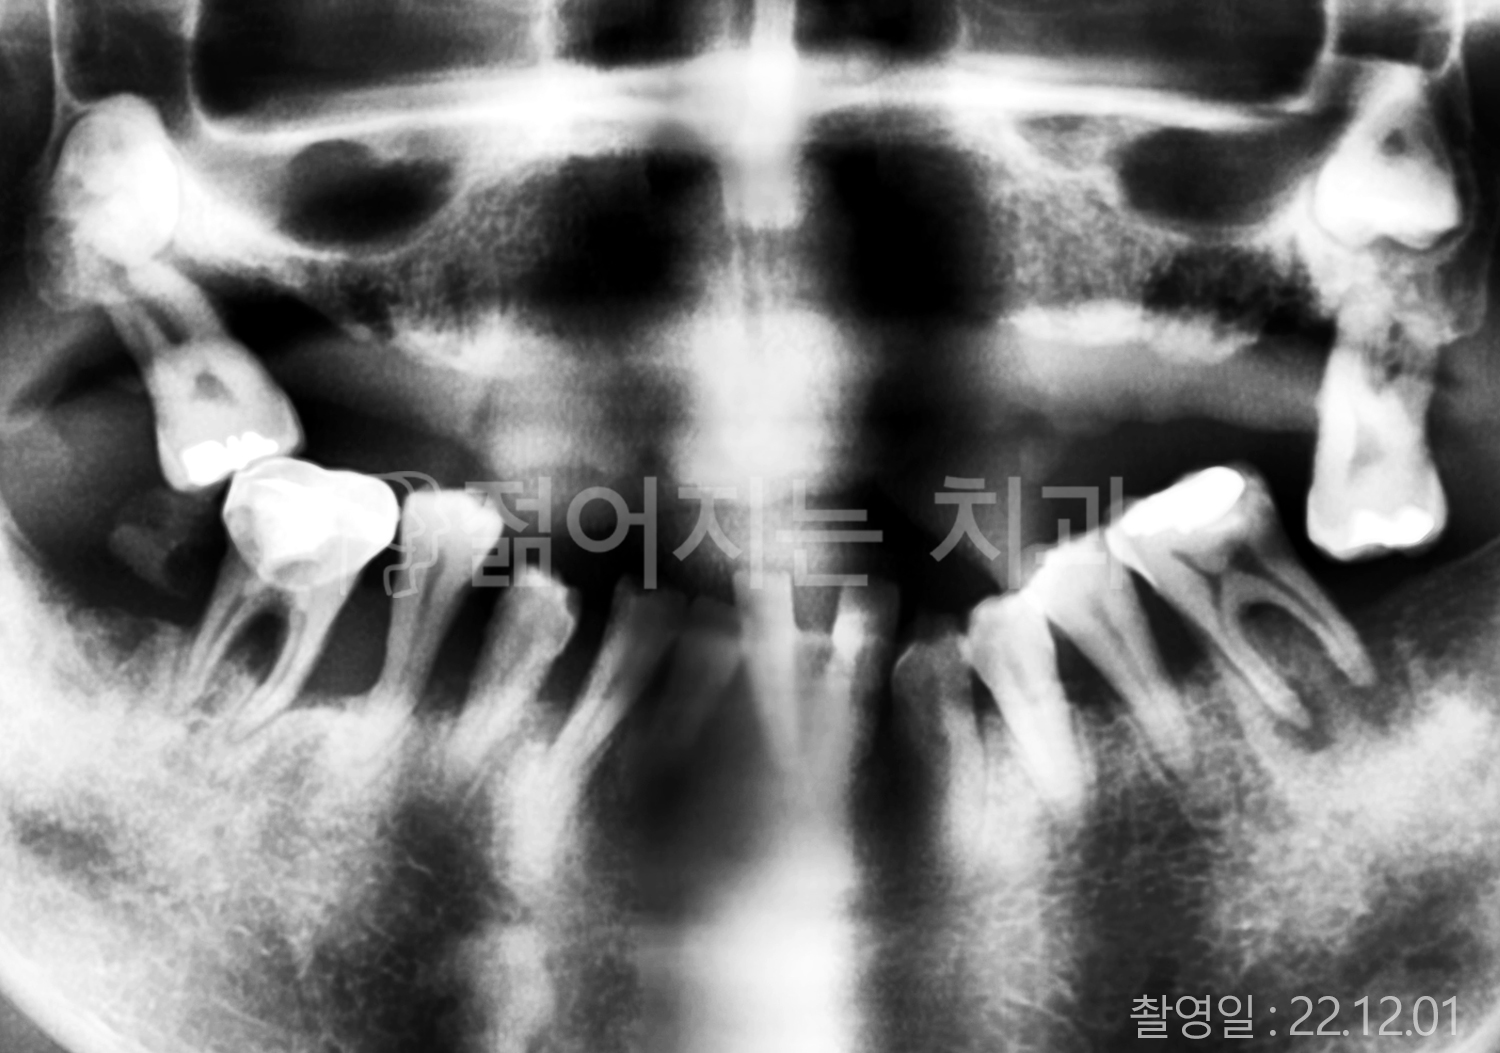

치료부위

식립개수

특이사항